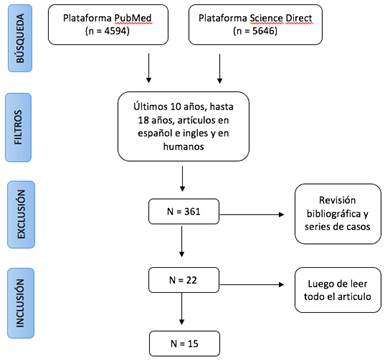

Se realizó en el mes de Octubre de 2019 la búsqueda bibliográfica sistematizada en los buscadores electrónicos PubMed y Science Direct. La búsqueda se realizó utilizando como término Mesh “Radial Fractures” y de manera manual agregamos “distal” y “treatment”, ya que este término no está indexado como Mesh. Se utilizó para agrupar dichos términos el operador booleano “AND”. Los filtros utilizados fueron artículos publicados entre 2009 y 2019, artículos en español e inglés, en pacientes hasta 18 años y en humanos

Para la selección bibliográfica se utilizó como guía para el diagrama de flujo protocolo de revisiones PRISMA (Figura 1).

De la búsqueda inicial en las diferentes plataformas surgieron un total de 4594 artículos en Pubmed y 5646 en Science direct (total 10240).

Colocando los filtros mencionados, se obtuvieron 361 artículos entre ambas plataformas. Luego de leer los títulos, se seleccionaron 22 artículos, que luego de leerlos completamente, fueron excluidos 7 artículos, resultando finalmente en 15 trabajos para nuestro trabajo.

Realizada la búsqueda por dos revisores independientes, se llegó al mismo número de artículos.